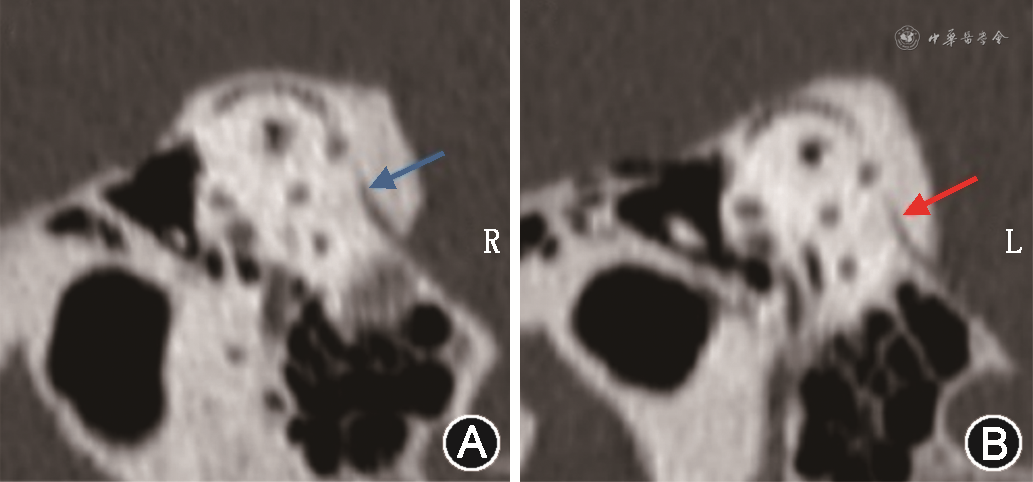

2021年7月5日9:10患者行耳蜗电图检查,-SP/AP振幅比左耳0.33、右耳0.20。检查结束后患者突发旋转性眩晕,耳部及植物神经症状与既往发作一致。发作初期可观察到水平向左的眼震,嘱患者卧床,送急诊肌注异丙嗪25 mg,返回后距发病约25 min,眼震已变为水平向右,眩晕、耳部及植物神经症状逐渐缓解。征得患者及家属同意后,于11:10再次接受磁共振扫描。此时距患者开始发作约2 h,眩晕已停止但仍有头晕,可见微弱的水平向右眼震。MIIRMR序列和i3D-real IR序列扫描见耳蜗、前庭积水均较前日减轻,并未观察到明显内外淋巴交混(图2E~H)。此次发作持续约3 h,发作结束后复查纯音测听,左耳平均听阈27 dBHL(图1B)。颞骨CT扫描示左耳前庭导水管较对侧狭窄(图3),左、右侧前庭导水管中点横径分别为0.46 mm和0.79 mm。